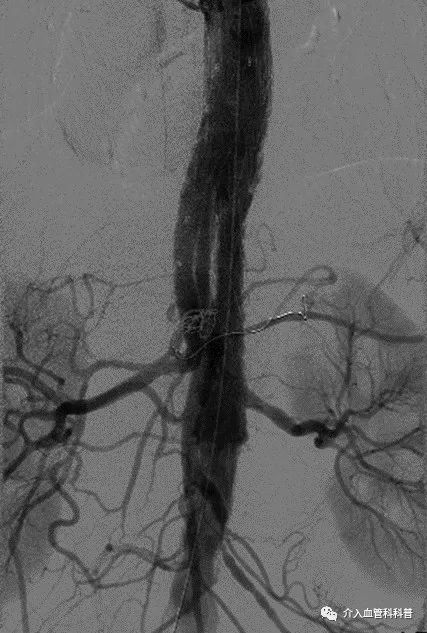

经过周密的术前准备,在麻醉与围术期医学科曹建主治医师的平稳麻醉下,周卫教授、唐新华教授、陈锋教授、以及熊清根博士同时上台操作,应用主动脉分支支架系统,在完全微创腔内技术下进行修复胸腹主动脉瘤,并重建双侧肾动脉、肠系膜上动脉的血供。

术后造影显示,患者胸腹主动脉瘤修复良好,无内漏,各内脏分支动脉血流灌注良好,术后患者康复出院。